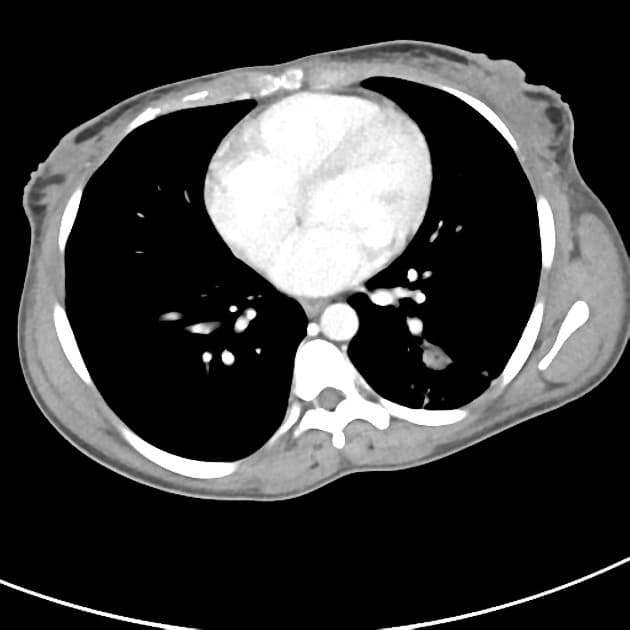

Axial non-contrast

Ghi nhận tình trạng ruột không quay với các quai ruột non nằm bên phải ổ bụng và đại tràng nằm bên trái. Góc tá hỗng tràng không bắt chéo qua bên trái đường giữa. Không thấy dấu hiệu tắc nghẽn.

Manh tràng nằm ở giữa ổ bụng với ruột thừa dài và giãn lớn đáng kể, đường kính đo được 20 mm với thành dày lan tỏa. Thấy hai sỏi phân ruột thừa trong lòng, với một viên kẹt tại gốc. Có tình trạng sung huyết và thâm nhiễm mỡ lan tỏa trong mạc treo ruột thừa kèm theo một vài hạch bạch huyết phản ứng, lớn nhẹ — không thấy tụ dịch quanh ruột thừa hay tạo khối choán chỗ rõ rệt.

Ít dịch tự do trong vùng chậu.

Gan nhiễm mỡ lan tỏa mức độ nhẹ. Nang thận phải nhỏ, đơn thuần.

Không thể tiêm thuốc tương phản do rối loạn các chỉ số chức năng thận.